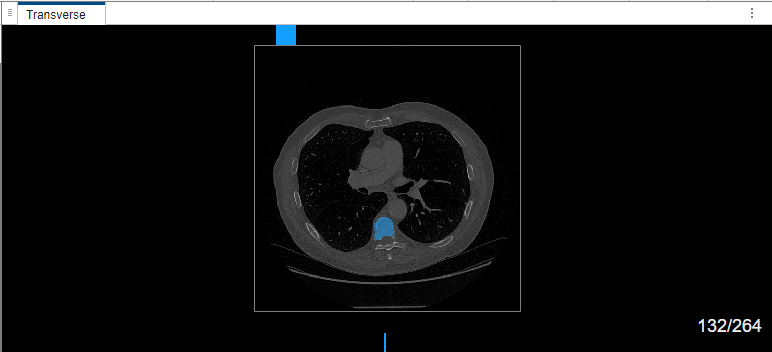

The MedSAM algorithm segments the object in the bounding box and labels it.